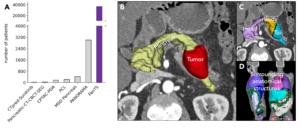

Dataset characteristics and visualization.

Aside from this impressive size and diversity, each CT scan in the dataset includes rich metadata—such as patient age, sex, diagnosis, and more—and information about imaging protocols and biomarkers to help enable AI models capable of identifying high-risk individuals across populations and imaging conditions, the researchers say.